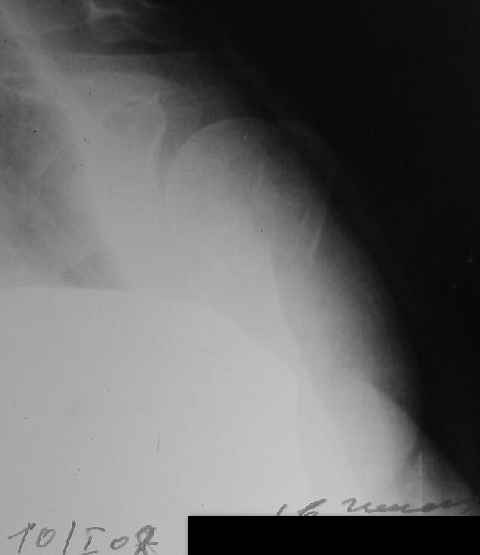

[Ortho] Comminuted fracture proximal humerus

CT scans would be useful to evaluate the head.

Another option could be closed nailing, see an example, the surgery was

done 2 days ago. In common such surgeries are performed under regional

anesthesia, not general.

Fragments now look severely displaced.